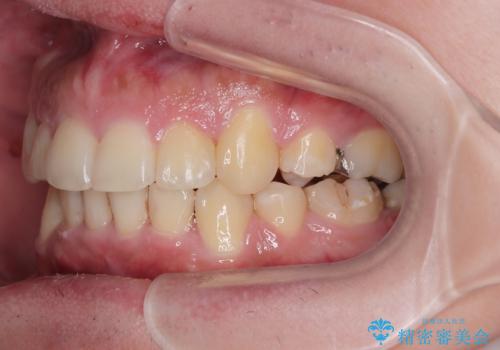

右上第一小臼歯は歯根癒着により移動せず、左上第二小臼歯は移動はするものの非常に動きが鈍かったため、抜歯したスペースを閉じるまでに非常に時間がかかってしまいました。

患者様には辛抱強く治療にお付き合いいただき、すっきりとした口元に仕上げることができました。